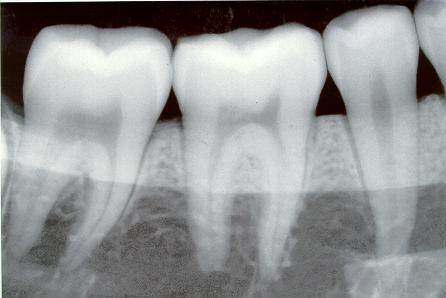

Гистологическое строение зуба (ткани, из которых состоит зуб)

- Эмаль – ткань, которая покрывает снаружи коронку зуба. Является одной из самых прочных тканей в теле человека, так как на 97% состоит из минеральных веществ. Толщина эмали в разных местах варьирует от 0,01 до 1,5 мм. Она максимальна на жевательной поверхности коронки.

- Цемент – ткань, которая по своему строению похожа на эмаль. Он покрывает зубной корень. Цемент и эмаль контактируют в области шейки зуба. Они могут соединяться встык, наезжать друг на друга. Иногда они не достигают друг друга, и тогда между ними остается промежуток.

- Дентин – основное вещество, из которого образованы зубы человека. Дентин состоит на 28% из органических веществ и на 72% — из неорганических. В дентине выделяют наружный и внутренний слой. Волокна, которые входят в его состав, проходя в тангенциальном и радиальном направлении, взаимно перекрещиваются. Это придает зубу дополнительную прочность. Внутри дентин имеет полость, которая внутри корней зуба переходит в корневые каналы.

- Пульпа – совокупность мягких тканей, находящихся внутри зубной полости и корневых каналов. В пульпе проходят сосуды и нервы зуба. В области верхушки зуба имеется отверстие, через которое пульпа переходит в ткани, окружающие зуб (ткани периодонта).

- Периодонт – ткани, которые расположены вокруг зуба в зубной альвеоле. Они фиксируют корень зуба в лунке, амортизируют нагрузки во время жевания, обеспечивают питание и нормальный рост зуба.